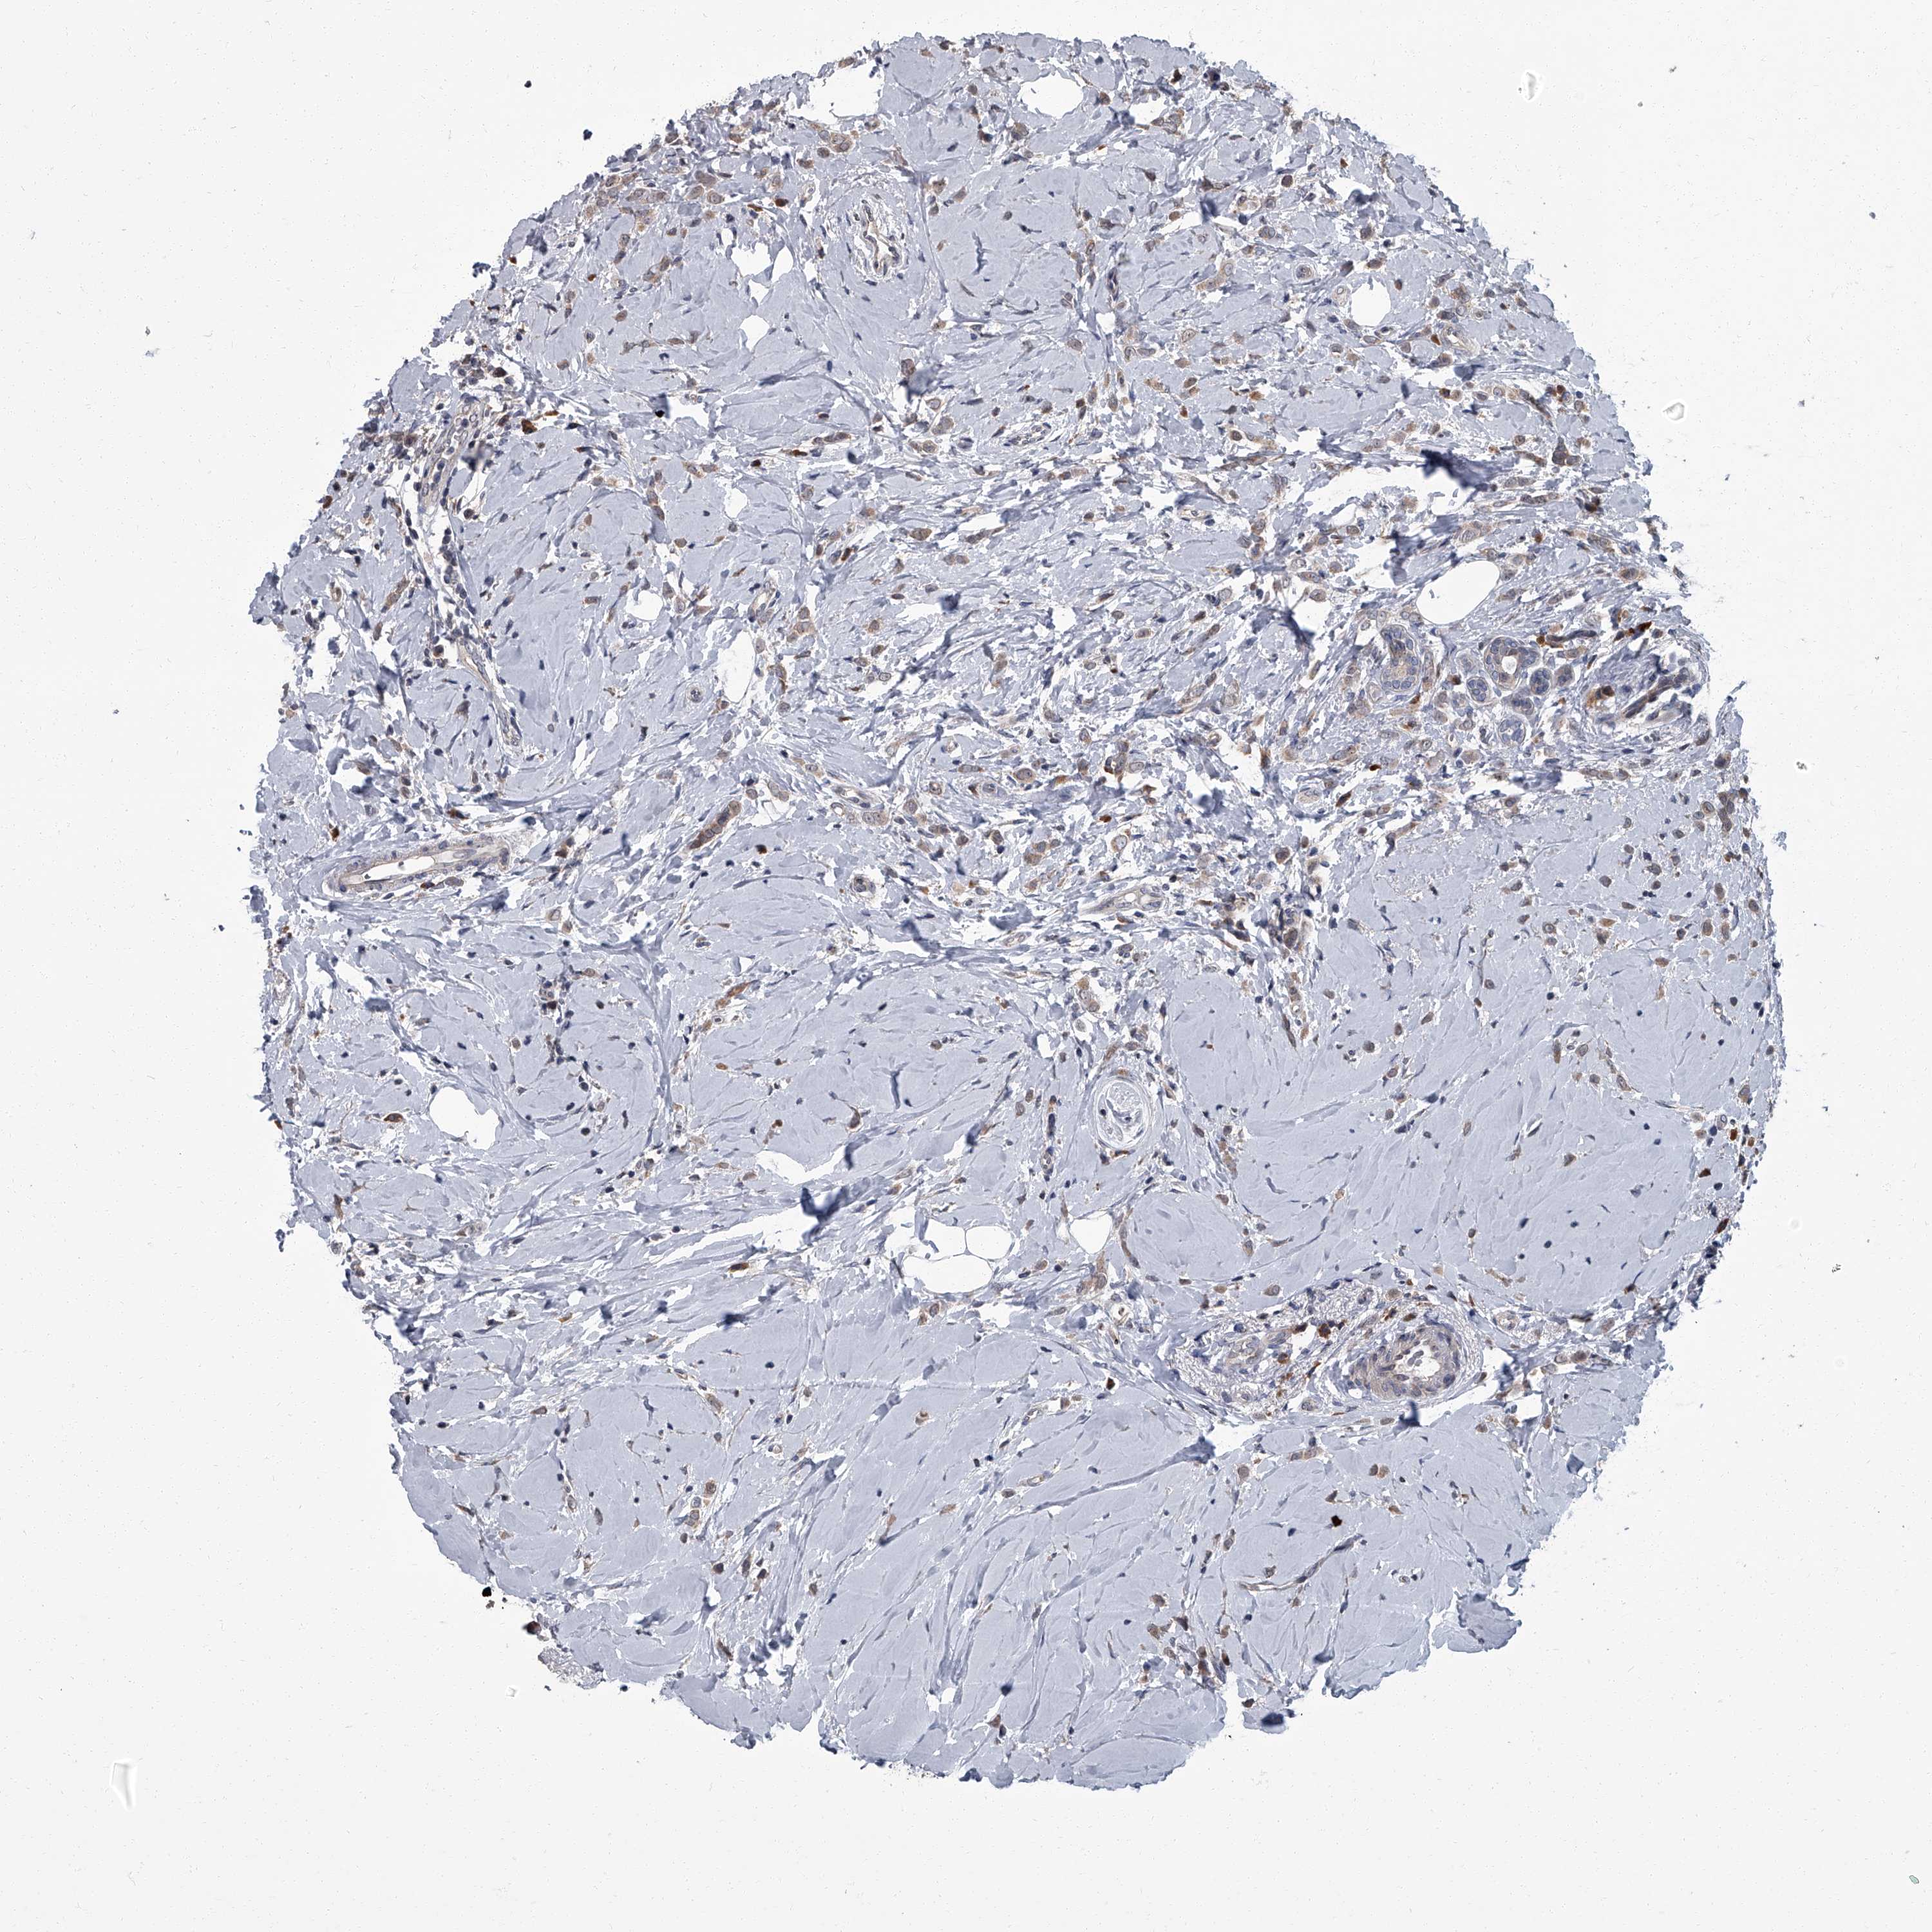

CANCER BREAST CANCER Show tissue menu

Breast cancer

Human cancer

ZNF274 is not prognostic in Breast Invasive Carcinoma (TCGA)